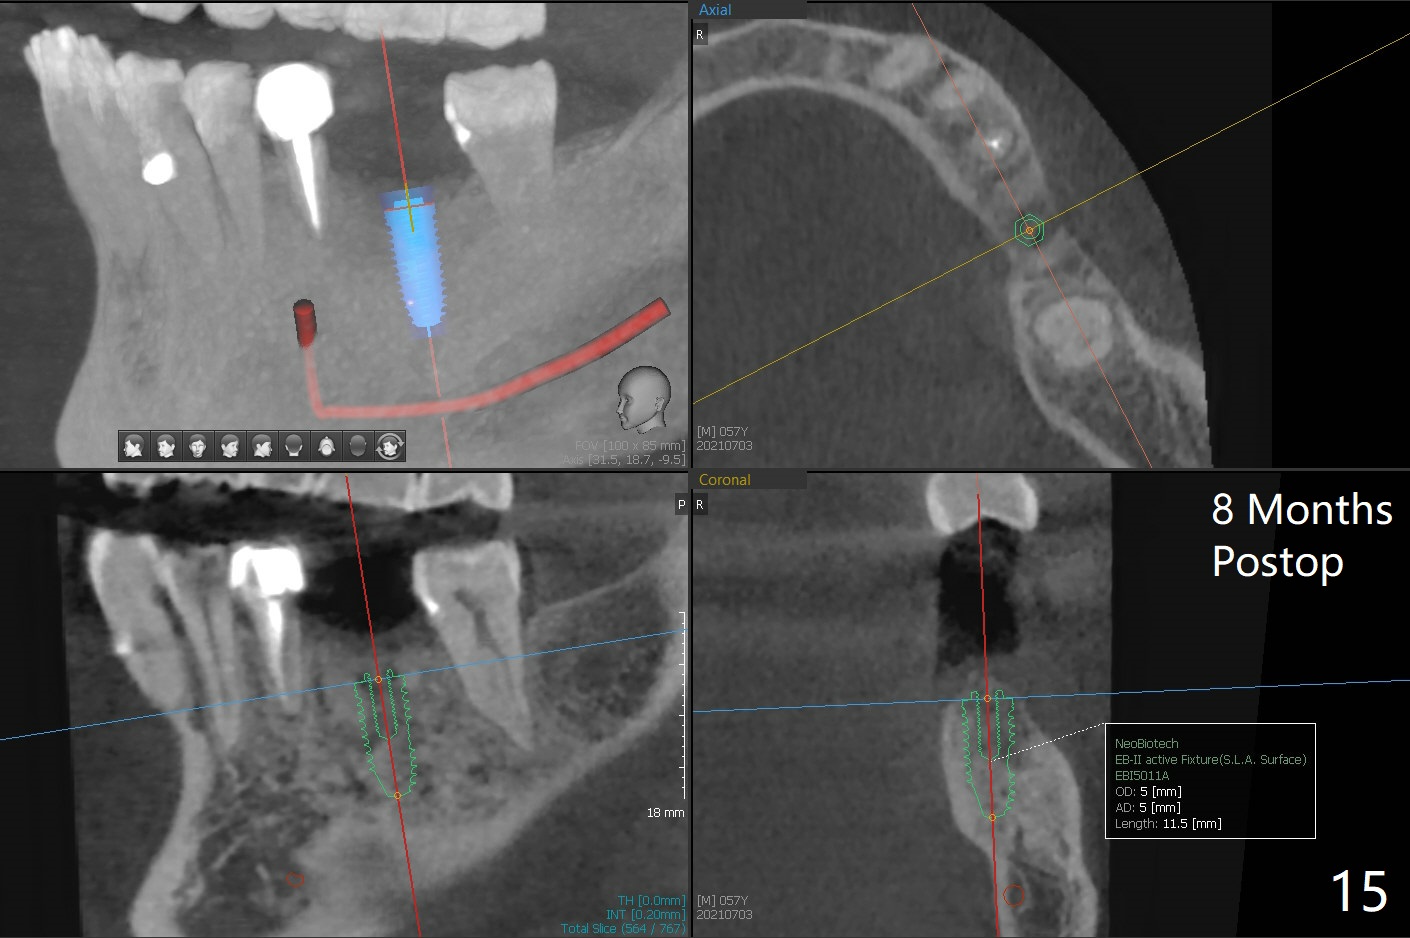

A 54-year-old man has distal (D) root fracture at #19 while the implant at #2 is osteointegrarting (Fig.1,2). Because of the large distal defect (Fig.3, after extraction), osteotomy (red line) will be initiated in the mesial socket (Fig.4, as distal as possible, with the coronal end in the middle of the socket) or the mesial slope of the septum (Fig.5) so that the implant (green) will be supported by the distally displaced septum (Fig.6 arrow). CT taken 8 months later confirms distal root fracture. A 6x11.5 mm or longer implant seems to be appropriate for the site (Fig.7). Three years later there is severe buccal swelling (Fig.8) with vertical mesial and distal root fractures (Fig.9). Although the buccal plate is lost, the septum remains (Fig.10 S), which will provide with blood supply to the bone graft (Fig.11), covered with Bioxclude and 6-month membrane and PSA suture. The bone density in the mesial and distal sockets is higher than that in the septum 8 months post cortical bone graft (Fig.12). In spite of bone graft, the buccolingual width reduces by almost 4 mm 8 months post extraction (Fig.3,4). In spite of bone graft, the buccolingual width reduces by almost 4 mm in 8 months post extraction (Fig.3,4). A 5x11.5 mm implant will be placed (Fig.15).